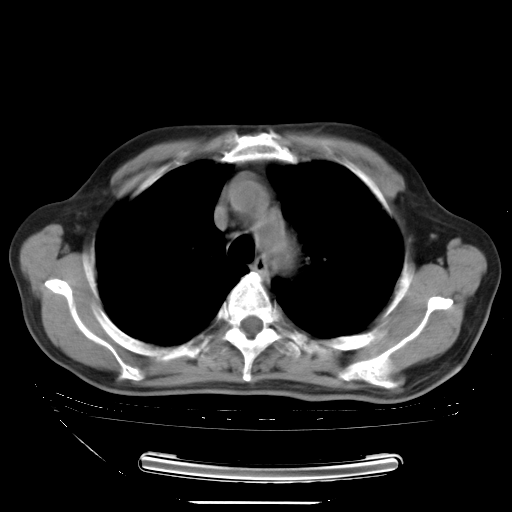

今天复查肺部CT,发现双肺广泛磨玻璃样改变。所以我把3月19日和5月9日相隔50天的肺部CT上传。请大家会诊。

5月9日肺部CT(在4月27日齐鲁医院肺部CT描述部分肺组织磨玻璃样改变,12天后肺组织广泛磨玻璃样改变)

大致读了系列胸部CT:纵隔窗无明显异常,肺窗:从4、27至今:主要是双肺中下野外带可见毛玻璃样改变,目前处于急性肺泡炎阶段,至于原因考虑1、结替组织或胶原血管性疾病所致?2、恶性疾病如恶组在肺部所致的表现或细支气管肺泡癌?3、药物或其它原因如肺蛋白沉着症所致肺泡炎目前不太可能?总之,明天就去请我院的呼吸科、感染科、血液科和临免专家会诊哈。